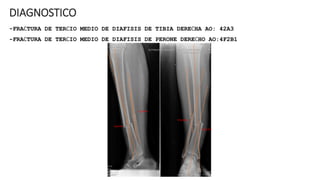

DIAGNOSTICO

-FRACTURA DE TERCIO MEDIO DE DIAFISIS DE TIBIA DERECHA AO: 42A3

-FRACTURA DE TERCIO MEDIO DE DIAFISIS DE PERONE DERECHO AO:4F2B1

INTRA QUIRURGICO (04/06/24)

-ENCLAVADO ENDOMEDULAR CON CLAVO UTN PARA TIBIA DERECHA

RX POST QUIRÚRGICO 04-06-24